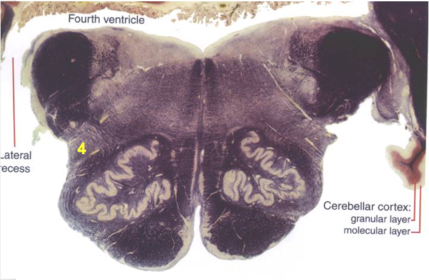

| CN IX | |

| Inferior cerebellar peduncle | |

| Inferior olivary complex | |

| Dorsal cochlear nucleus | |

| Inferior vestibular nucleus | |

| Medial vestibular nucleus | |

| Spinal nucleus of V | |

| Spinal tract of V | |

| Medullary pyramids | |

| Solitary nucleus | |

| ALS | |

| Medial lemniscus | |

| Medial longitudinal fasciculus | |

| Ventral cochlear nucleus | |

| Anterior spinocerebellar tract | |

| Central tegmental tract | |

| Olivary internal arcuate fibers | |

| Solitary tract | |